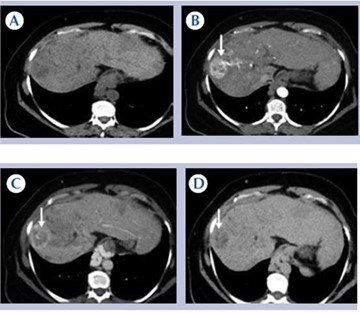

Colangiocarcinoma

El colangiocarcinoma es una neoplasia maligna originada en el epitelio de las vías biliares. Representa el segundo tumor más frecuente del sistema hepatobiliar, por detrás del carcinoma hepatocelular. La mayoría son adenocarcinomas independientes de su localización en el hígado.

El Liver Cancer Study Group of Japan, en 2009, propuso una clasificación basada en el patrón de crecimiento tumoral, que es muy útil para el diagnóstico por imagen, ya que describe la apariencia macroscópica de la infiltración y de esta manera se complementa con los hallazgos encontrados en las pruebas de imágenes permitiendo realizar un diagnóstico diferencial. Clasifica los tumores en tres grupos: los formadores de masa, los de infiltración predominantemente periductal (Anexo 16) y los de crecimiento intraductal. Existe predominio de un patrón de crecimiento u otro en función de la localización topográfica: el colangiocarcinoma intrahepático suele debutar como una masa, mientras que en los colangiocarcinomas hiliar y extrahepático predomina la infiltración periductal.

El reforzamiento en anillo (hipercaptación periférica) o incluso menos de 25% de la lesión, y es más frecuente en nódulos mayores a 3 cm. En la fase venosa portal puede permanecer invariable cuando los nódulos son pequeños. Puede presentar un reforzamiento progresivo: existiendo el máximo realce en fases tardías (más frecuentes en nódulos de mayor tamaño). También puede demostrar un reforzamiento continuo con área central que no capta el medio de contraste. En la fase tardía la región central puede mostrar un reforzamiento variable en función de la existencia de fibrosis (aumento de la captación) o necrosis coagulativa (sin captación del contraste).(18-22)